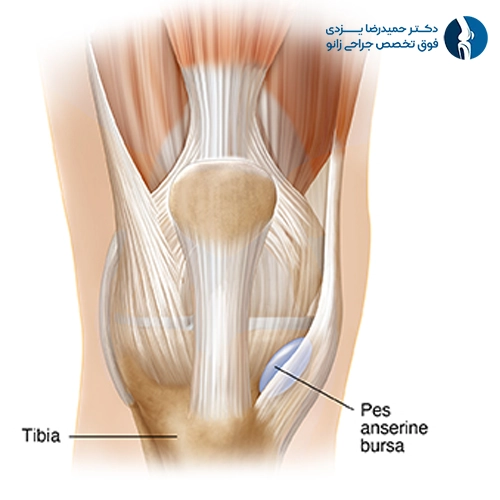

بورسیت پسدرشتنی (Pes Anserine Bursitis)

این نوع بورسیت در ناحیه داخلی و پایین زانو، جایی که تاندونهای سه عضله همسترینگ به استخوان درشتنی متصل میشوند، ایجاد میشود. این بورس نقش مهمی در کاهش اصطکاک بین تاندونها و استخوان ایفا میکند و بیشتر در افراد چاق، دوندگان، یا کسانی با زانوی پرانتزی یا پای صاف دیده میشود.

علائم آن شامل درد داخلی زانو، بهویژه هنگام بالا رفتن از پله یا نشستن طولانیمدت است. تورم معمولاً زیاد نیست، اما درد بهصورت عمقی احساس میشود. لمس ناحیه داخلی زانو ممکن است همراه با حساسیت باشد.

درمان شامل کاهش وزن در بیماران چاق، فیزیوتراپی برای تقویت عضلات چهارسر و همسترینگ، مصرف داروهای ضدالتهاب و کمپرس سرد است. در موارد خاص، تزریق داخل بورس میتواند مؤثر باشد. تصحیح اختلالات مکانیکی مانند صاف بودن کف پا نیز در پیشگیری از عود بیماری مفید است.